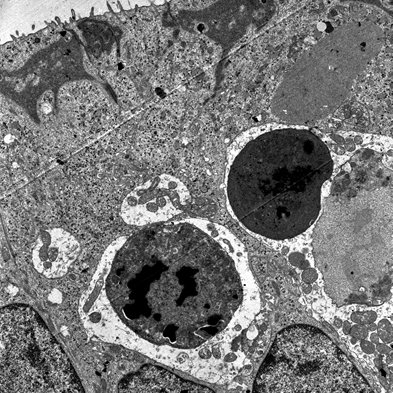

(8/14) In the article now published, we used RNAseq to identify gene expression changes occurring during these early steps in chronic #haircells ototoxicity. We crossed results from 5 different control vs. experimental comparisons.

(5/14) Before final extrusion, #vestibular #haircells must follow a complete program of morphological alteration. So we aimed at understanding the process.

(2/14) Many stress conditions, including exposure to specific toxic agents (ototoxicity), cause degeneration of the #vestibular sensory #haircells. This causes permanent loss of #vestibular function, because the #haircells are unable to regenerate and reestablish proper function